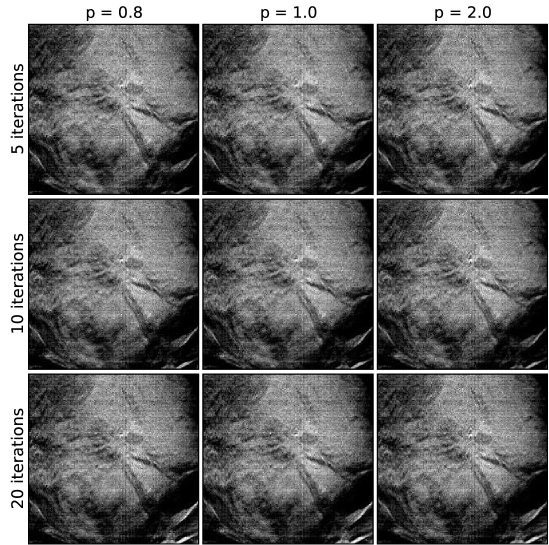

Each of the three cases, below, are reconstructed in the same way, meaning the same sets of algorithm parameters are used. The exceptions to this are that the image volume dimensions and the projection data cropping are slightly different for each case. For the EM results images are shown at 5,10, and 20 iterations, as iteration number is really the main control for regularization. For ASD-POCS, the objection function parameter is set to 0.8, 1.0, and 2.0; lower values of tend to sharpen edges. The relaxation factor takes on values of 1.0, 0.5, and 0.1; smaller , in general, allows for ASD-POCS to achieve lower values of the TpV objective. Images for ASD-POCS are also shown for 5, 10, and 20 iterations. As will be seen, there is surprisingly little change in the reconstructed images for these iteration numbers. In each of the image sets, a 2D ROI is displayed that shows either microcalcifications or a mass, depending on the case.

V.4 Case 1: microcalcifications

A set of EM images for the first case is shown in Fig. 4, and the corresponding ASD-POCS images are shown in Figs. 5, 6, and 7. A striking feature of the ASD-POCS reconstructions is the prominence of the microcalcifications. Lower values of accentuate these small features better than large -values. Even for , the visibility of the microcalcifications is comparable to that of the EM results. The differences in microcalcification contrast can be seen quantitatively in the profiles shown in Fig. 8. These profiles are plotted along depth and transverse lines that intersect with a single microcalcification. We point out that while lower increases regularization strength in ASD-POCS and lower iteration number increases regularization strength for EM, there is no direct correspondence between the two parameters; the chosen iteration numbers for the EM profiles are selected only for reference. Interestingly, there seems to be little change in the ASD-POCS image for iteration numbers 5-20, which obviously has some practical implication.

From the profiles and slice images, it is clear that lower in ASD-POCS enhances microcalcification contrast substantially, leaving one to wonder if there is any advantage to larger -values. While lower -values appear to be advantageous, there is also an impact of -value on the image background. The ROIs displayed in Figs. 5, 6, and 7 are shown in a large enough region to obtain some sense of the difference in background. Again, we are trying, here, to only give some intuition on the parameter-space dependence of the ASD-POCS algorithm. Optimal values of and for particular tasks, such as microcalcification detection by human observers, need to be investigated in separate studies. Another important factor that affects selection of and is data quality. Lower values of , for example, may be robust against detector noise, but may be also more sensitive to inconsistency due to patient motion.